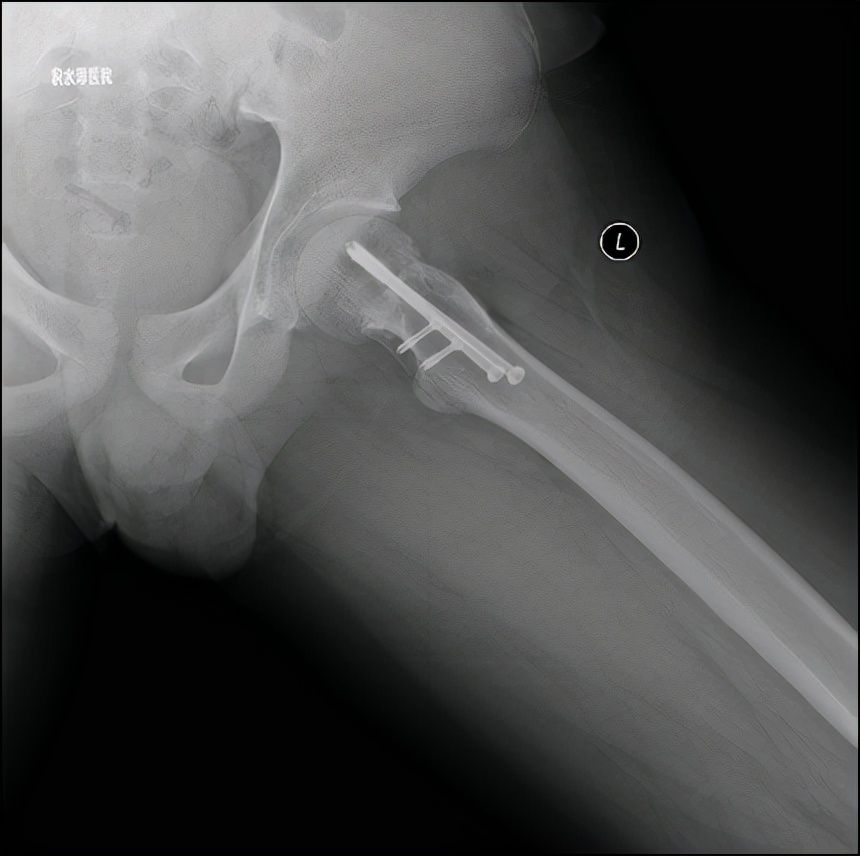

病例2 男,14岁,右侧重度SCFE,行闭合复位,经皮空心钉固定术

病例2 术中股骨头骺内实时血供监测显示复位后,股骨头血供良好

病例2 术后17个月复查,X线示位置良好,无股骨头缺血坏死发生